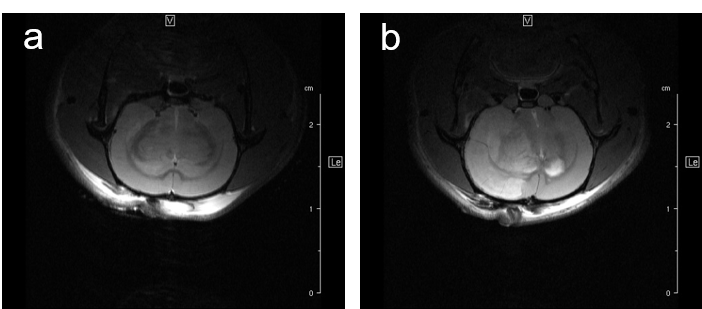

For studying disease pattern of stroke patients, we use a rat animal model with induction of focal cerebral ischemia and follow-up by MRI, Fig.7.

Fig. 7: Infarcted rat brain MRI. For comparison of infarct size of induced infarct right after OP and 24 h later a T2 weighted Spinecho sequence was used: repetition time: 3800 ms, echo time: 18.0 ms, field of view: 35x35 mm2, matrix:512x256 and slice thickness 1.0 mm was used to acquire 12 axial slices.